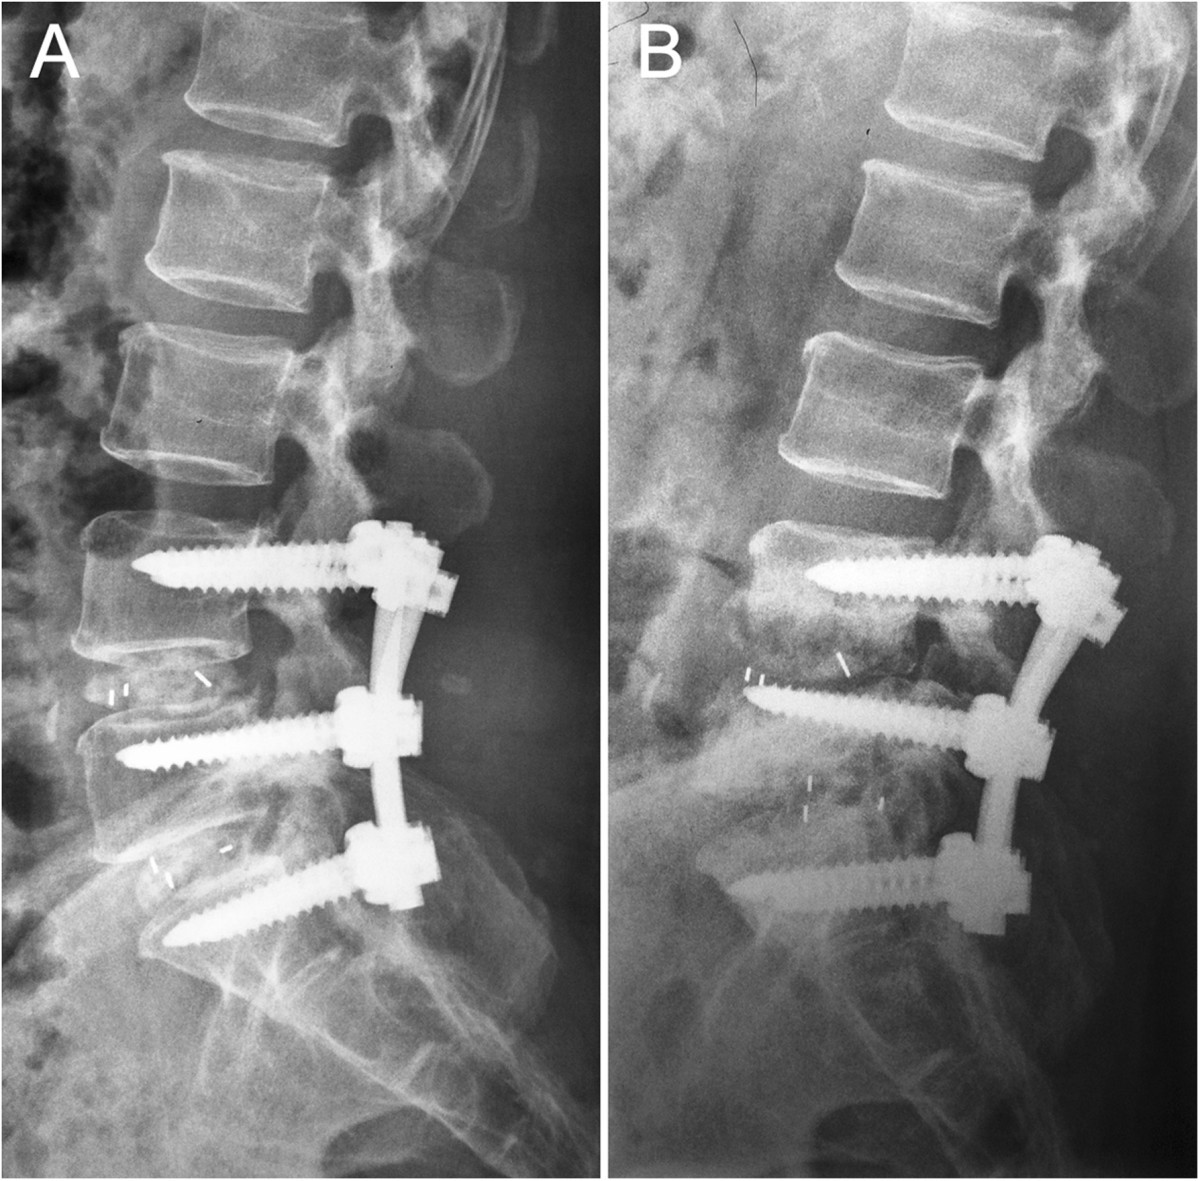

КТ-протрузии дисков: Визуализация и классификация

Раздел: Необычные решения